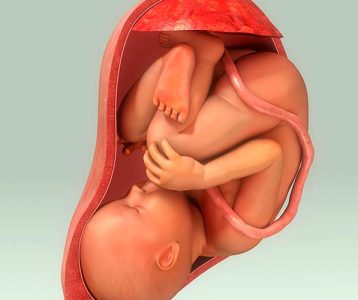

A predisposição genética desempenha um papel significativo para os desvios de coluna, especialmente na escoliose idiopática. Esse problema, que é mais comum durante a adolescência, pode ocorrer ao longo do crescimento. Além disso, lesões traumáticas na coluna, como fraturas vertebrais, podem resultar em desvios caso não sejam adequadamente tratadas.

Toda coluna saudável tem um leve grau de curvatura para dar mobilidade à estrutura e ao tronco corporal como um todo. Sendo assim, os problemas ocorrem quando estas curvaturas anormais da estrutura vertebral são acentuadas. Esses desvios, que dependem da região, envolvem escoliose, hipercifose e hiperlordose.

Na escoliose ocorre um desvio acentuado da coluna para os lados, formando um S (ao ver a pessoa de costas). Na hiperlordose, a acentuação se dá para a frente, na altura da região lombar, causando a proeminência dos glúteos. Enquanto na hipercifose ocorre um aumento anormal da curvatura da região cervical, no alto da coluna.